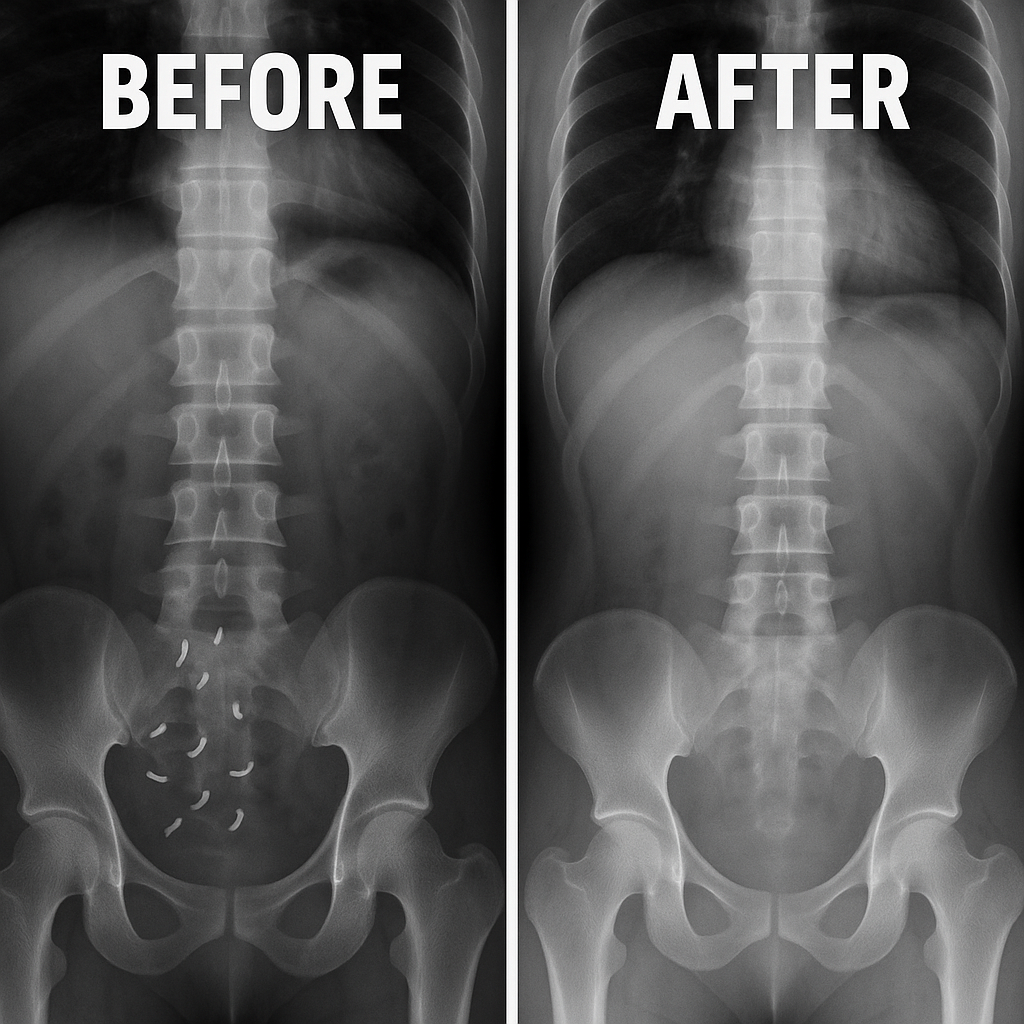

Your Journey to A Parasite Free Life

With just a few capsules, you'll gently detox, restore balance,

and start feeling like yourself again.

Noticeable Relief Begins

Early signs of change: reduced bloating, smoother digestion, and better energy throughout the day. You may start to feel lighter—physically and mentally.

Balance in Motion

As internal systems recalibrate, gut and immune functions become more stable. Brain fog lifts, energy stays more consistent, and your mood feels more even.

Full-Body Reset

This is where it all comes together—improved focus, stronger immunity, and a more resilient digestive system. You feel more vibrant, clear, and in control of your wellness.